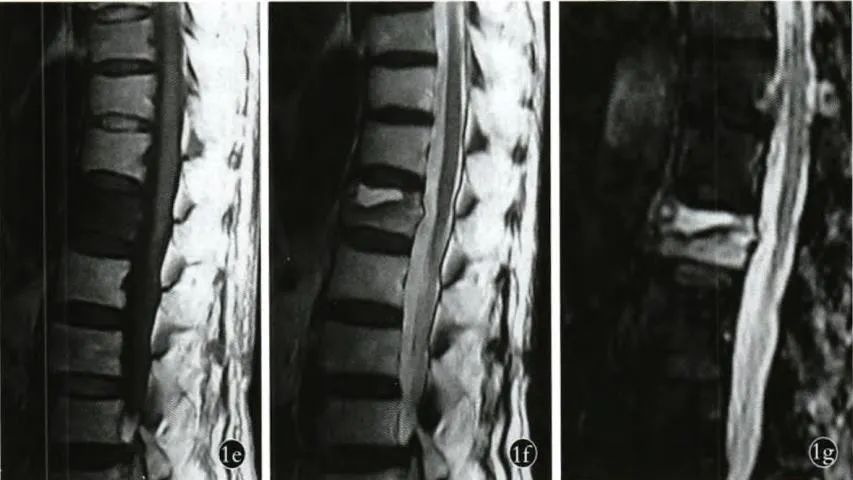

在MRI上Kümmell病表现出与周围界限清晰边界完整的信号变化区域,T1加权像呈低信号,T2加权像及STIR像呈高信号(图1 e,f,g),形成“双线征”。

图1e,f,g MRI示病椎前方上终板下方病变区域T1加权像上呈低信号,T2加权像及STIR像相应区域呈边界清晰完整的高信号。